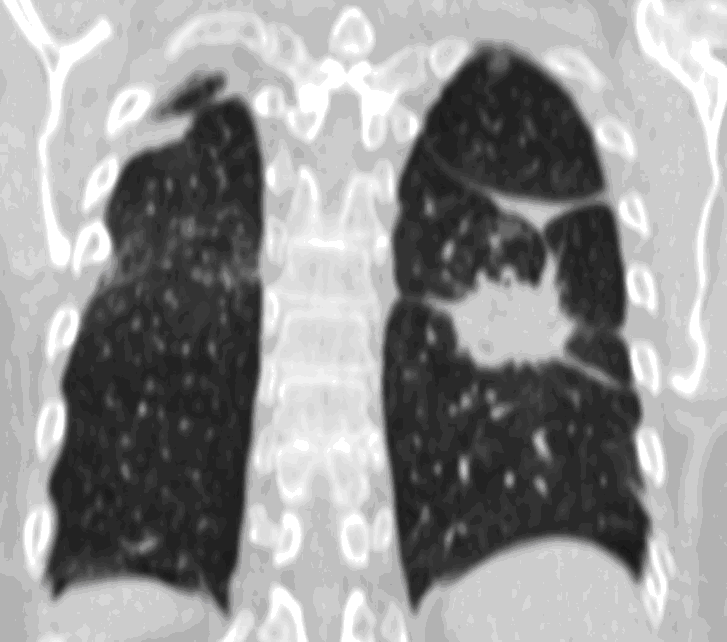

20. Miliary lung metastases. HRCT, coronal reconstruction:

60 year old man, secondary pulmonary lesions due to kidney tumor, underwent target therapy.

Lobulated nodule in the left lung, associated with the pleura dorsobasally.

Lobectomy because of right lung adenocarcinoma, (brain metastasis). (by the contribution of Zsuzsanna Monostori, MD, PhD)